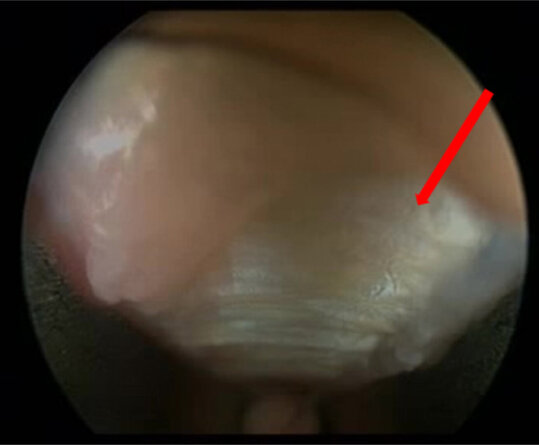

Aufgrund der anatomischen Ursache ist eine operative Therapie die Methode der ersten Wahl, um das Karpaltunnelsyndrom dauerhaft erfolgreich zu behandeln. Über viele Jahrzehnte wurde eine offene Spaltung des sog. Ligamentum carpi transversum – der Bandstruktur, die den Karpaltunnel „überdacht“ – durchgeführt. Seit einigen Jahren werden zunehmend endoskopische Techniken zur Spaltung des Ligamentum carpi transversum erfolgreich angewandt. Die langfristigen Ergebnisse sind vergleichbar mit denen der offenen Operationstechnik.

In der hiesigen Klinik für Neurochirurgie werden sowohl die offene Technik als auch die endoskopische Technik regelmäßig angewandt.

Es stehen verschiedene operative Verfahren zur Verfügung. Über viele Jahre wurde eine langstreckige Dekompression mit anschließender Verlagerung des N. ulnaris zur Ober-/Unterarminnenseite standardisiert mit guten Ergebnissen durchgeführt. Alternativ dazu haben sich zunehmend operative Techniken mit alleiniger Dekompression des N. ulnaris in seinem Verlauf in der Ellenbogenrinne durchgesetzt. In den letzten Jahren wird zunehmend auch die minimal-invasive endoskopisch-assistierte Technik angewandt. Auch in unserer neurochirurgischen Klinik wird ein großer Anteil der Patienten in der endoskopisch-assistierten Technik nach Hoffmann operiert.